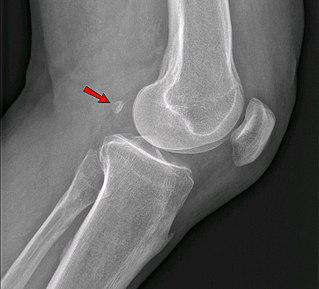

Человек эволюционирует и сегодня: у него появляются новые кости (на илл.) и артерии.

Фабелла — небольшая сесамовидная кость, обнаруженная у некоторых млекопитающих, встроенная в сухожилие боковой головки икроножной мышцы позади латерального мыщелка бедренной кости. Это дополнительная кость, анатомическая вариация, присутствующая у 39 % людей. В редких случаях таких костей бывает две или три. Эту кость можно принять за дряблое тело или остеофит. Слово fabella — это латинское уменьшительное от слова faba, означающего «фасоль».